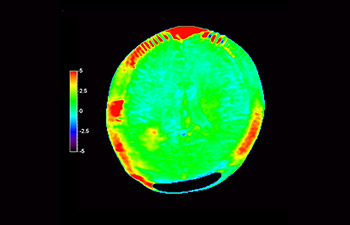

Glioblastoma recurrence

Brain imaging for glioblastoma recurrence

with 3D APT

3D APT (Amide Proton Transfer) is a unique, contrast-free, brain MR imaging method addressing the need for more confident diagnosis in neuro oncology. 3D APT uses the presence of endogenous cellular proteins, to produce an MR signal that directly correlates with cell proliferation, a marker of tumoral activity. 3D APT can support trained medical professionals in differentiating low grade from high grade gliomas and, in differentiating tumor progression from treatment effect1.